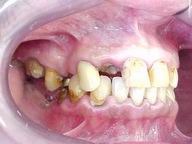

Reabilitação funcional e estética em ambas as arcadas

com próteses fixas e removíveis de encaixe de precisão.

ANTES

Vista Lateral Direita